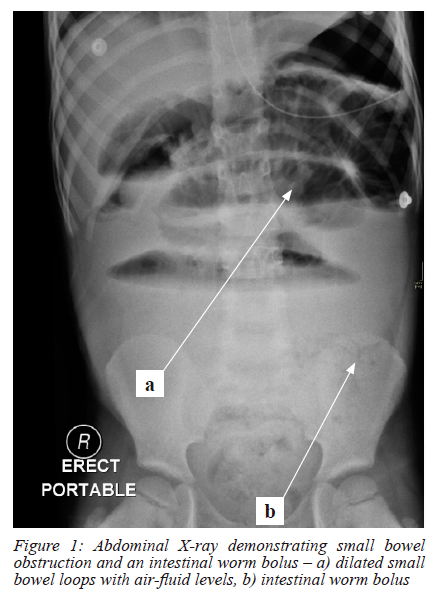

An abdominal X-ray demonstrated features of small bowel obstruction with a worm bolus visible within the small bowel (Figure 1). Arterial blood gas analysis revealed a compensated metabolic acidosis (pH 7.37, bicarbonate (HCO3) 14.8 mmol/l, base excess - 7.8 mmol/l, lactate 1.2 mmol/l and pCO2 3.3 Kpa) (normal ranges pH 7.35 -7.45, HCO3 22 - 26 mmol/l, base excess -2 - +2 mmol/l, lactate < 2 mmol/l and pCO2 4.7 - 6.0 Kpa respectively). Blood analysis showed a raised white cell count at 20.12 x 109/L (normal values 6.00 - 16.00 x 109/L). Of note, the eosinophil count was normal at 0 x109/l (normal values 0.0 - 0.5 x109/l) and haemoglobin was slightly elevated for his age at 15.4 g/dl (normal values 9.5 - 14 g/dL).

Diagnostic images for small bowel volvulus include plain abdominal X-rays that may identify small bowel obstruction and an abdominal contrasted tomography (CT) scan. An abdominal CT scan may demonstrate a characteristic whirlpool sign, however the accuracy to identify small bowel volvulus can be as low as 45%.8 Intestinal ascaris can sometimes be identified on plain abdominal X-rays. A large cluster of worms can be seen, highlighted by intestinal gas, with an irregular border between the worm mass and the surrounding gas shadows. Individual worms may appear as linear or bubble-shaped radiolucency.9